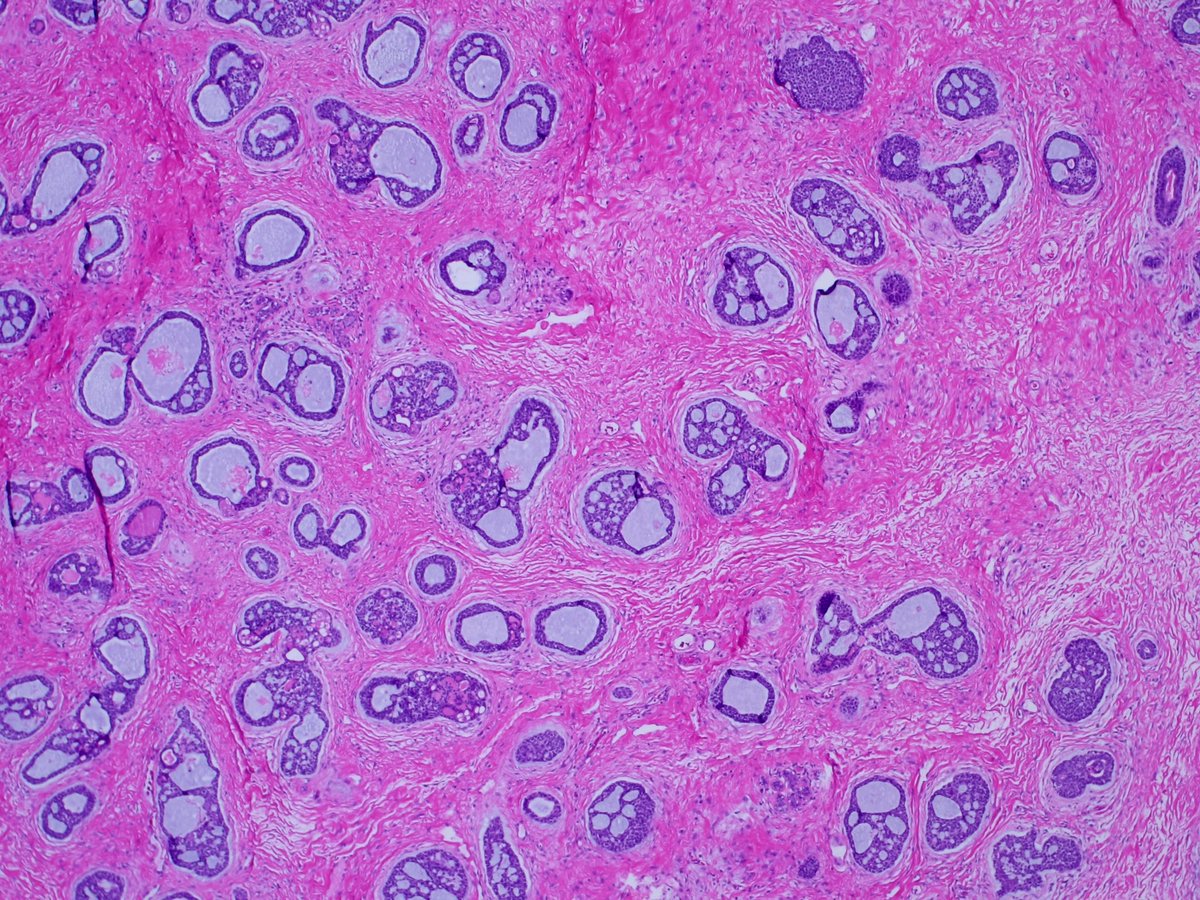

1. #Breastpath, with an #ENTpath flavor A case I had which pairs well with this sweet diagram by@TheKarenPinto (linked below) 40 year old woma